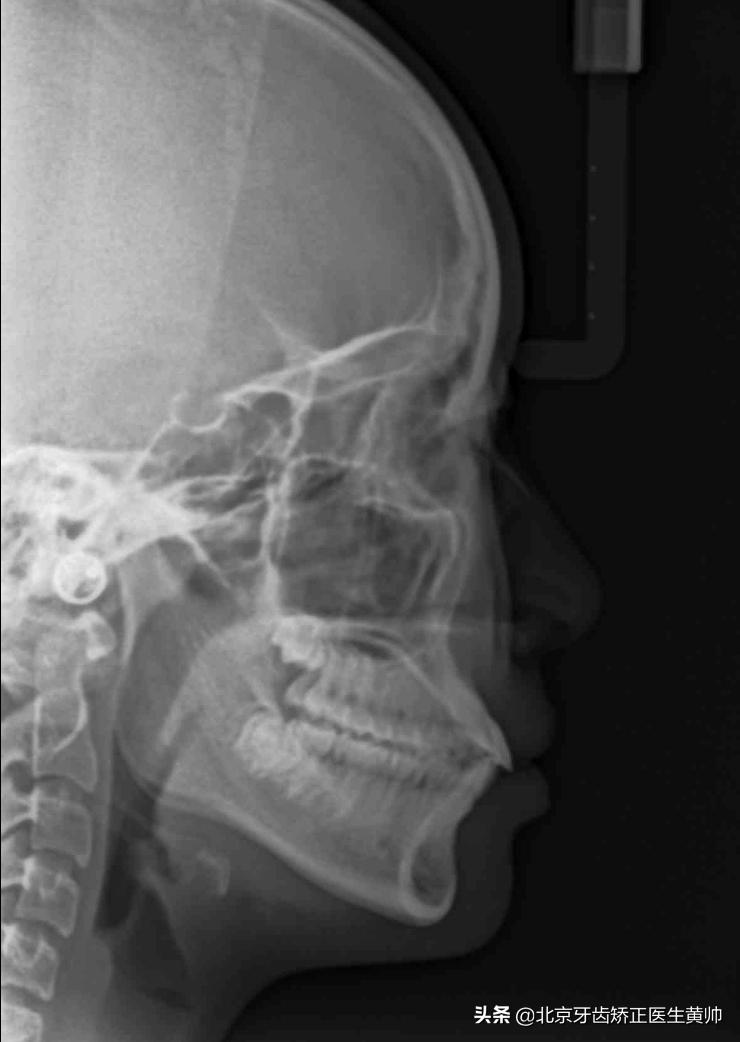

在孩子进行牙齿矫正之前,有必要做一下相关的检查,包括面部以及牙颌照片、拍摄头颅侧位片和全口曲面断层片等。

头颅侧位片